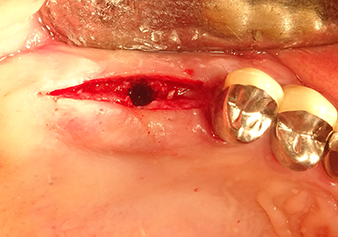

Implant bed preparation and augmentation

Following an intermediate check (Fig. 4) a further preparation step was performed (Fig. 5). Afterwards, the hydraulic Z35P instrument was used to lift the membrane to the desired position (Fig. 6 and 7). This was followed by further piezosurgical preparation of the implant bed, concluded with a rotary bur and shoulder milling cutter up to the implant diameter of 4.8 mm. Before the implant was inserted, the augmentation material (particle size approx. 0.8-1.6 mm) was introduced underneath the Schneiderian membrane (Fig. 8).

Implantation and prosthetic restoration

To move the augmentation material in the direction of the maxillary sinus atraumatically, the implant was inserted very slowly by hand (Fig. 9). In the process, the membrane was pushed in the cranial direction once again. After two months, the surgical site healed without irritation. Six months later, the x-ray check showed a significant increase in opacity as an indication of ossification (Fig. 10). The prosthetic restoration was carried out with a metal-ceramic crown.